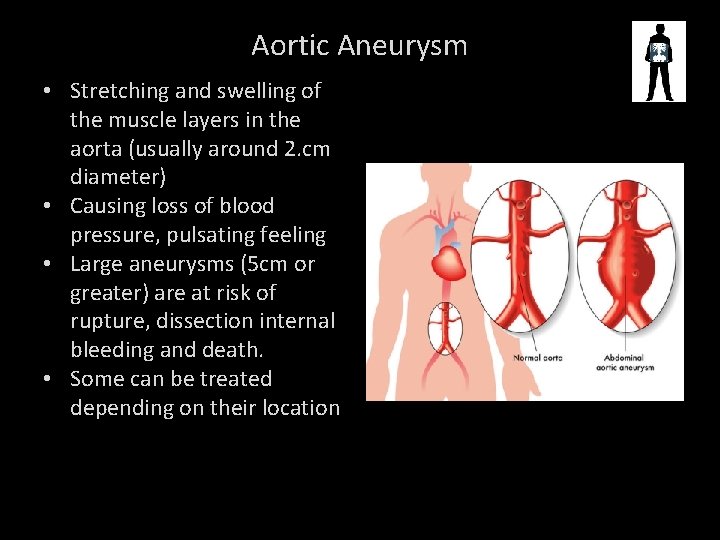

ABDOMINAL AORTIC ANEURYSM

Aortic Aneurysm • Stretching and swelling of the muscle layers in the aorta (usually around 2. cm diameter) • Causing loss of blood pressure, pulsating feeling • Large aneurysms (5 cm or greater) are at risk of rupture, dissection internal bleeding and death. • Some can be treated depending on their location